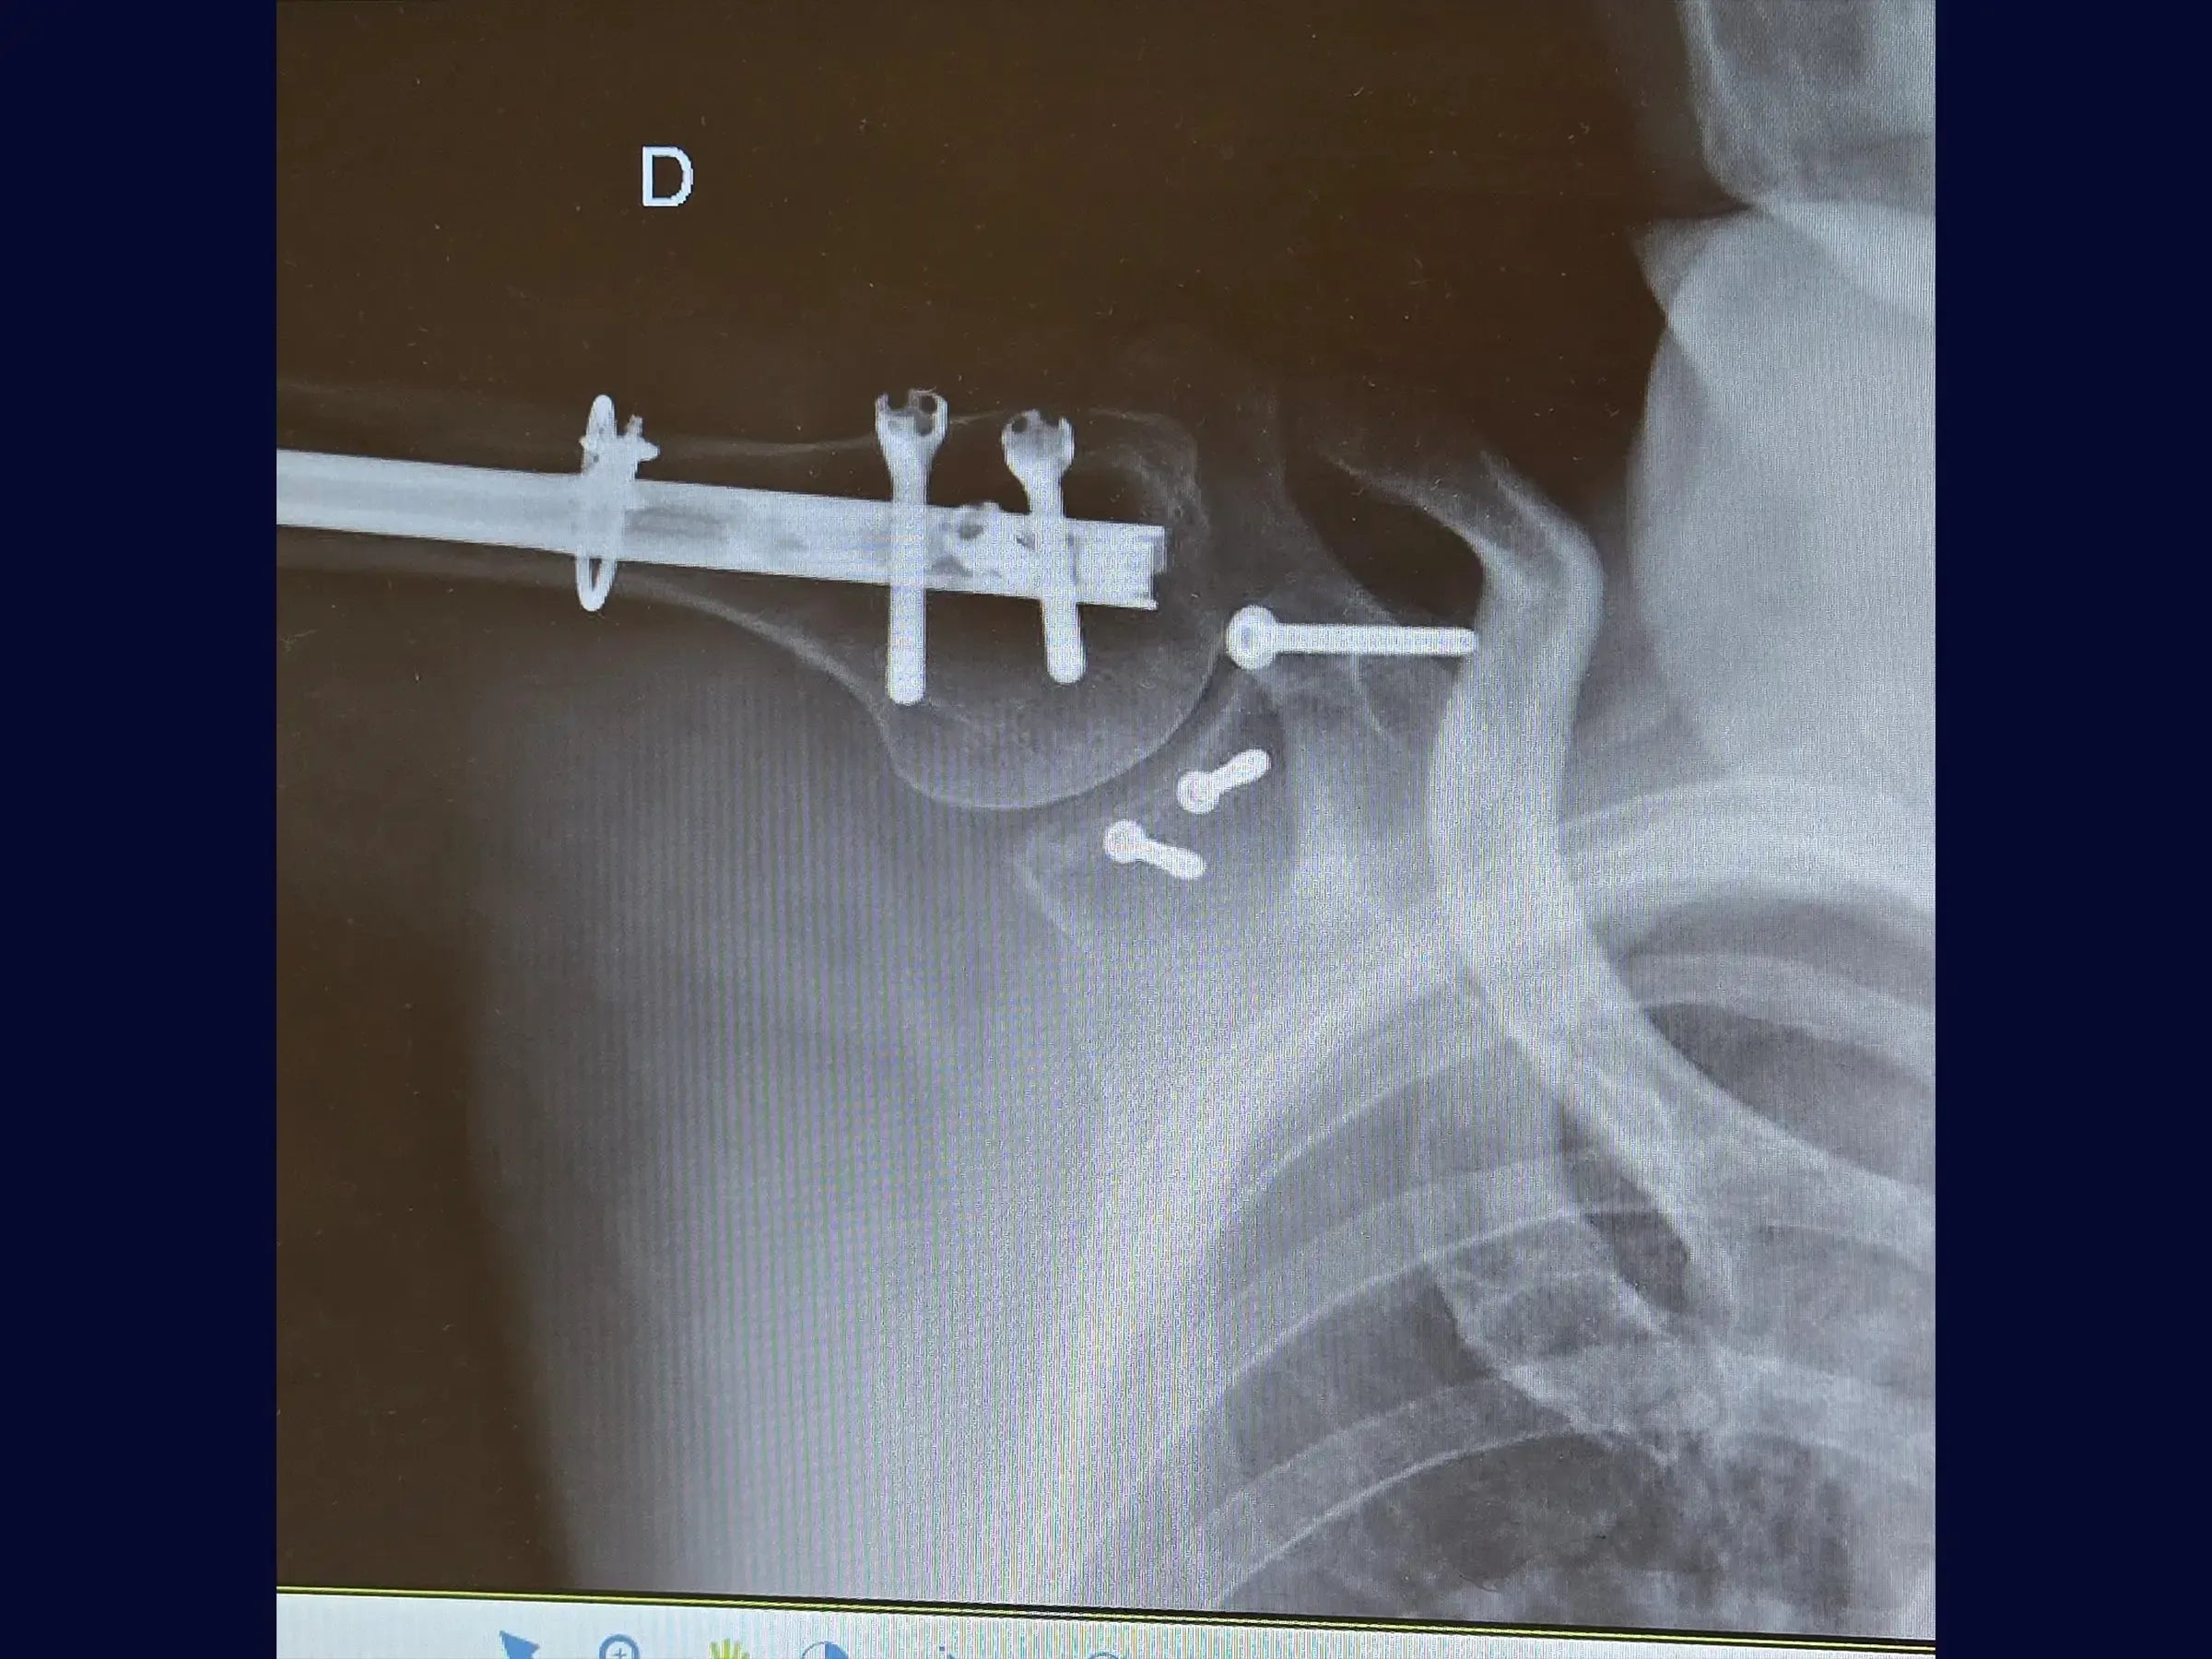

- Osteossíntese com haste intramedular e cerclagem no úmero.

- Fixação com parafusos na glenoide e coracoide.

- Reconstrução Segmentar do Úmero: Abordagem sistemática para identificação dos vértices da fratura, redução do segmento proximal e fixação com haste intramedular e parafusos proximais, complementada por cerclagem, para estabilidade e restauração anatômica.

- Fixação Precisa da Glenoide: Técnica de incisão e separação do subescapular da cápsula articular para exposição e redução do fragmento da glenoide, com inserção de fios guia e parafusos para assegurar a congruência articular e estabilidade.

- Estabilização do Coracoide: Demonstração da fixação do processo coracoide, preso ao tendão conjunto, com parafuso de compressão.

- Fechamento Anatômico e Prevenção de Complicações: Protocolos de sutura da cápsula e subescapular, e fechamento do acesso deltopeitoral para minimizar sangramento pós-operatório e hematoma, otimizando o resultado funcional.